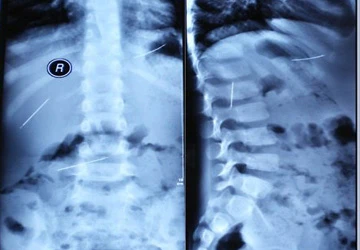

| Hình ảnh cho được từ chụp cộng hưởng từ hay MRI cho thấy có ba cây kim trong cơ thể cậu bé. |

Khi đang chơi gần nhà, Tiểu Diệp bị một chiếc xe đụng phải, khiến cậu bé bị thương ở đầu, bụng, lưng… và được đưa đến bệnh viện. Sau chiếu chụp, các bác sĩ ở bệnh viện Phúc Châu sửng sốt phát hiện có ba vật lạ như cây kim trong gan, thận và bụng của cậu bé.

Không thể tin vào mắt mình, những ngày sau, các bác sĩ tiếp tục chiếu chụp cho Tiểu Diệp, mời thêm các bác sĩ Nhi khoa khác đến kiểm tra. Ngày 22.4, các bác sĩ xác định được ba vật lạ trong người cậu bé là cây kim.

Các bác sĩ đã lần lượt gắp ra ba cây kim khâu bình thường, mỗi cây dài 3cm, điều lạ là hai cây kim trong số ba cây kim lại quay ngược lên chứ không đâm vào cơ thể, và một trong số đó đã có bắt đầu dấu hiệu bị gỉ.